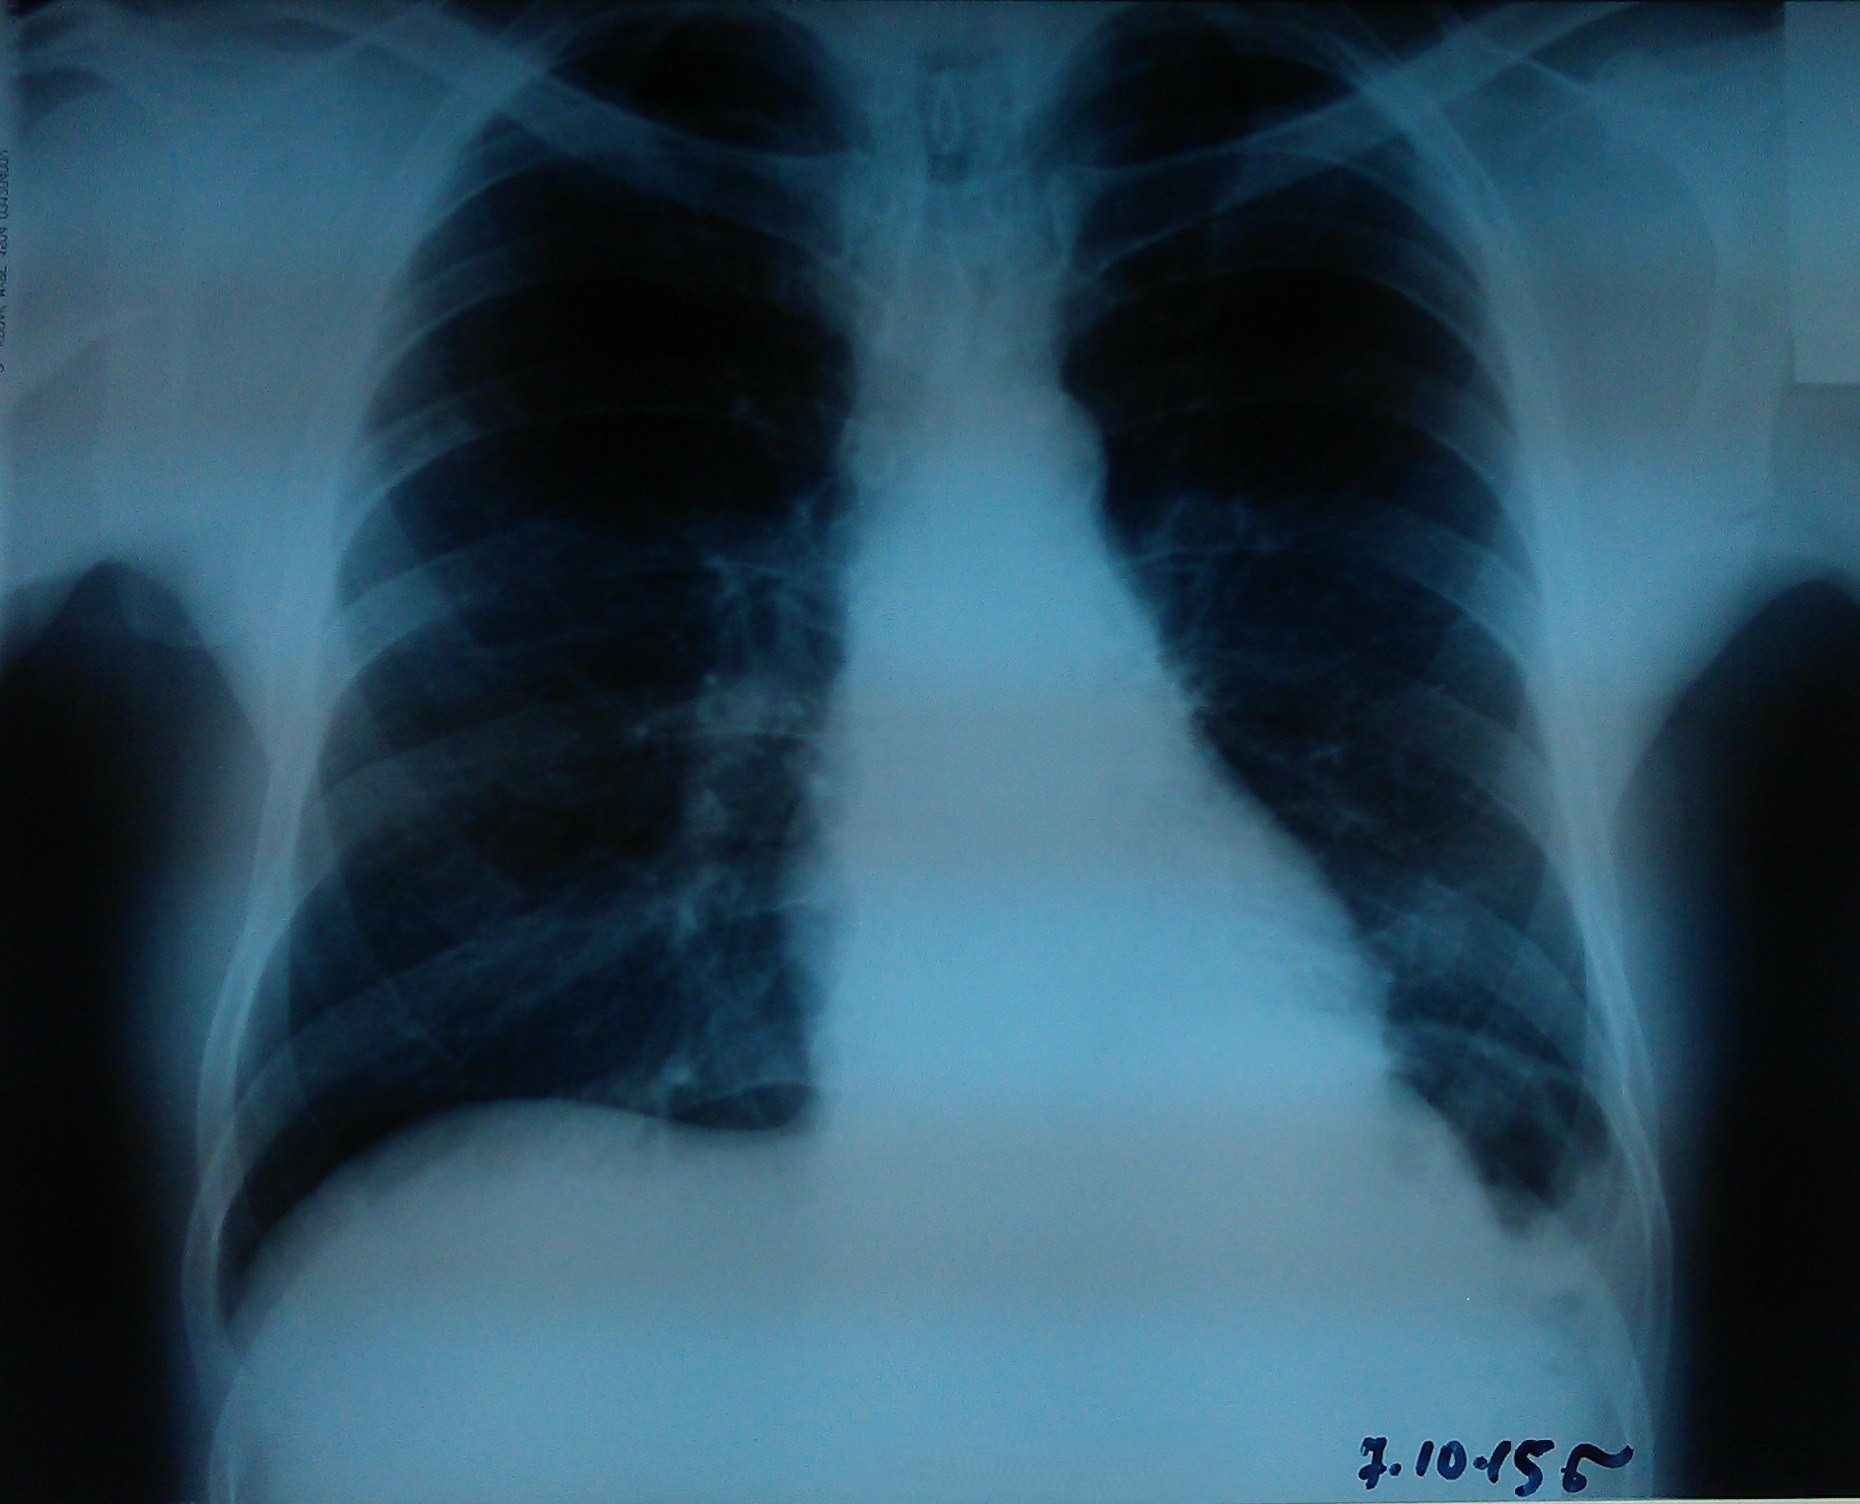

- გულმკერდის რენტგენოგრაფია სტენტირებიდან 4 დღეში

მარცხენა ფილტვი ნაწილობრივ გაშლილია.